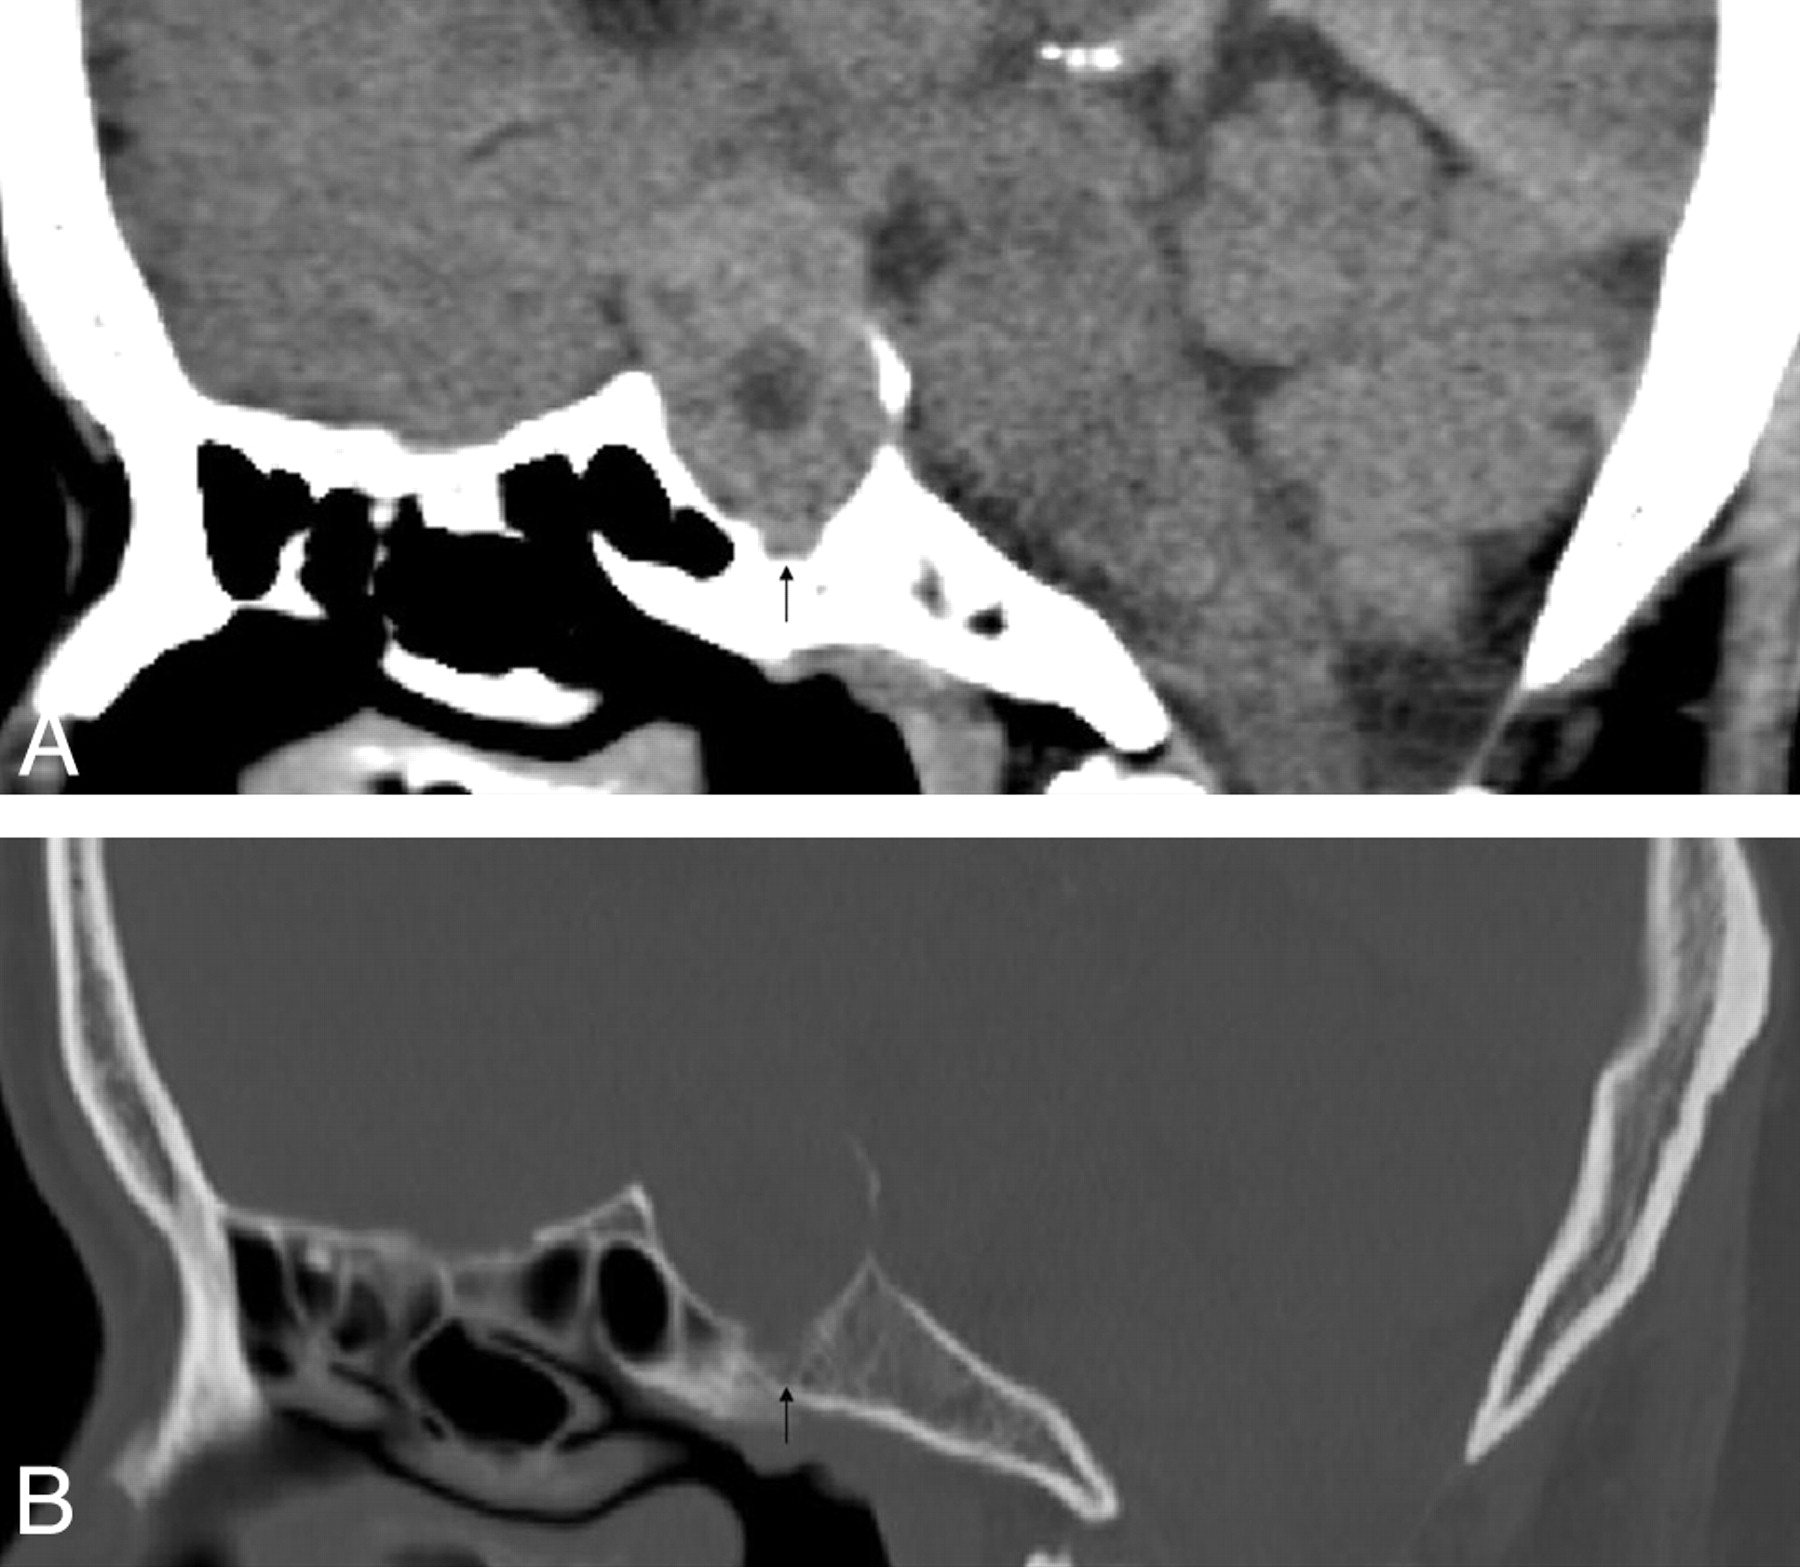

Larger tumor volume correlated with higher frequency of clival invasion (Table 3). The 32 tumors with clival invasion were significantly larger than those in the 358 patients without invasion (Table 2, P < .001), and 25 tumors with extensive clival invasion (18.90 ± 9.05 cm3, Fig 1A, -B) were significantly larger than those in the 7 patients with localized invasion (14.04 ± 3.35 cm3, P = .038, Fig. 2A, -B). In addition, the mean volume of the 142 null-cell macroadenomas (7.69 ± 11.37 cm3) was significantly larger than that of the 248 secreting tumors (4.87 ± 6.59 cm3, P = .006). Nevertheless, despite correction for the significant correlation of tumor volume with pathologic subtype (r = −0.247, P < .001), an independent correlation persisted between tumor volume and clival invasion (b = −.050, P < .001, OR = 0.951).

Soft-tissue (A) and bone algorithm (B) sagittal MPR in a 43-year-old male patient with a null-cell pituitary macroadenoma, producing focal clival invasion (black arrow). The tumor volume is 17.02 cm3.